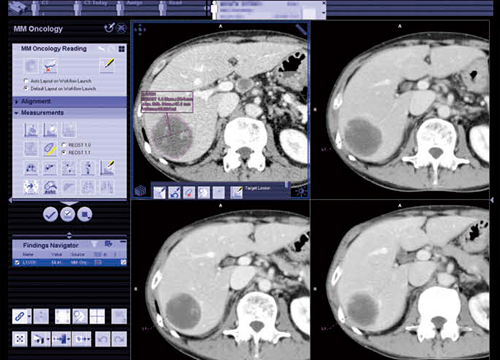

●MM Oncology

MM Oncologyでは,PET・SPECTなどの機能画像や,CT・MRIなどの解剖学的画像に対して,閲覧,操作,三次元処理,比較が行える。これまで,視覚的に比較し評価されてきた形態的・機能的な変化を,半自動的に解析,評価し,結果をレポートとして文書化することも可能だ。特に,強力な位置合わせ機能と,多様な測定ツールを備えていることが特長である。

2)病変の測定・認識

病変の測定・認識(Auto Segmentation)機能では,病変部分を横切る直線も選択することで,ワンクリックで病変輪郭,最大径の認識,体積測定などが行える。図5は,肝転移症例だが自動的に輪郭が認識されており,1つのスライスで病変を認識すると,別のスライスでも自動的に適用され,同じ病変を連続したボリュームとして観察・測定可能である。Auto Segmentationの測定パラメータとしては,肺,肝臓,リンパ節,一般の4つのプロトコルがあり,病変に応じて使い分けることができる。

また,Auto Segmentationでは,1つのシリーズのあるスライスで病変(L1)を設定すると,ほかのスライスの同一病変と思われる部分が自動的に認識されるほか,過去画像でも認識して,連続して測定,解析が可能になっている。同一スライス上に複数病変がある場合でも,病変ごとに認識することが可能である。

図5 MM Oncology

肝転移症例のAuto Segmentation